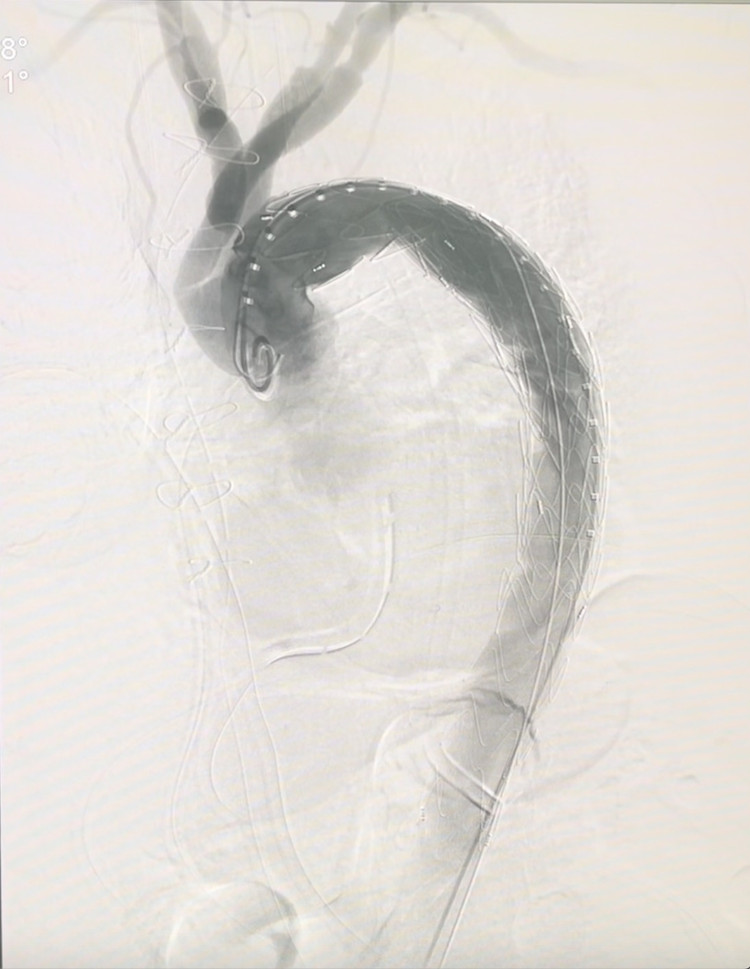

Hình ảnh lóc tách động mạch chủ sau can thiệpHình ảnh lóc tách động mạch chủ sau can thiệp